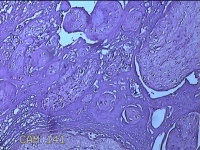

胎盘组织

性别

女

年龄

30岁

临床诊断

妊娠合并中度贫血

一般病史

停经39+2周,B超检查发现羊水偏少6小时。

标本名称

大体所见

灰白暗红色胎盘组织16.5x14.5x3.5㎝一个,表面光滑,血管突出,颜色发暗,绒毛面结节状,有轻度糜烂,暗红色,有少许凝血块,切面见绒毛内有暗红色血液渗出,边缘蜕膜可见多个小血肿,脐带39x1.8x0.3㎝,螺旋状扭曲,切断脐带,见脐血管内有凝血块。